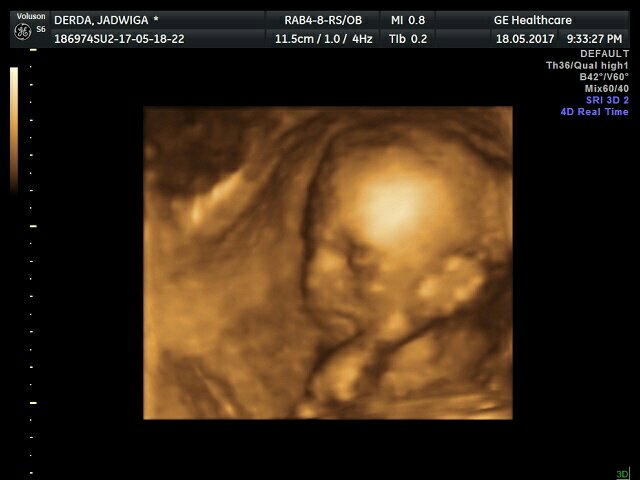

1495194458-aaaaaa.jpeg

Trochę zmienił położenie ale jest mocno wtulony w łożysko i ciężko było zrobić ładne zdjęcia ale coś się udało.

1495194514-aaaaaa.jpeg

1495194530-aaaaaa.jpeg

Najlepsze jest to, że według Polskich pomiarów jest mniejszy ale w normie więc się nie martwię.